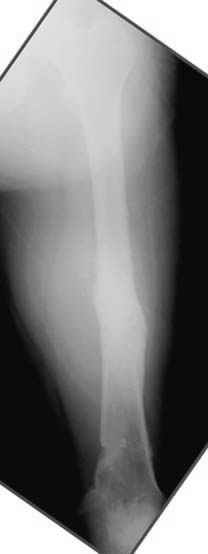

пластическая модель; и коррекция бедра аппаратом Илизарова.

хотя даже если бы и инфекция , то nail exchange с рассверливанием канала - вариант дебрайдмента) Я думаю, что последовательность развития событий:

Узкий к-м канал - тонкий гвоздь- усталостный перелом дистальных винтов - развитие нестабильности и как ее результат остеолиз вокруг гвоздя - деформация анатомической оси бедра. Похоже, что я понял почему аппарат, а не новый гвоздь:-)

ЕТ - Изначально костно-мозговой канал бедра был узкий, дальнейшее его рассверливание ещё больше скомпрометирует прочность бедра( латеральный кортекс дистального отломка уже истончен), приведет к дефекту наружной стенки - хотя это только мои догадки - хотелось бы знать мнение Джолдаса о выбранной тактике.